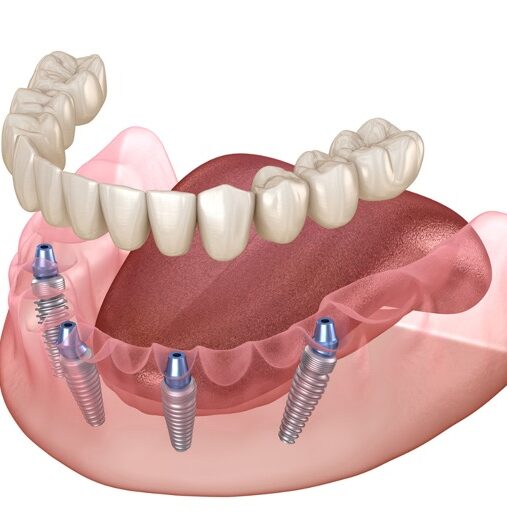

All-on-4 Tedavisi

All-on-4 Tedavisi Özellikle arka bölgedeki dişlerin uzun süre önce çekildiği, üst çenede sinüsün